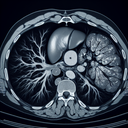

МРТ органів черевної порожнини

Магнітно-резонансна томографія (МРТ) органів черевної порожнини - це неінвазивний метод діагностики, який використовує магнітні поля і радіохвилі для отримання детальних зображень внутрішніх органів. ### Процедура підготовки: 1. **Консультація:** Спочатку проводиться консультація з лікарем, де ви обговорите необхідність МРТ, медичну історію та можливі протипоказання (наприклад, наявність імплантів чи клаустрофобії)...